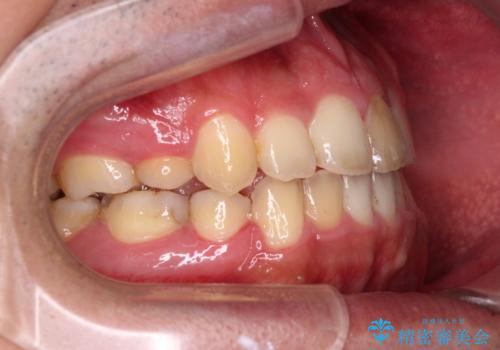

後戻りでデコボコの前歯 インビザライン矯正治療

- 高校時代に行った抜歯矯正が後戻りをしたとのことで来院された患者様です。

再矯正であることから、目立ちにくい装置を希望されたため、インビザラインにて矯正治療を行うこととしました。

下顎骨が左側に変位しているため、正中が合わないことは予想できましたが、歯列が整った後も咬み合わせが安定せず、咬み合わせを落ち着かせるために1年以上の期間を要しました。